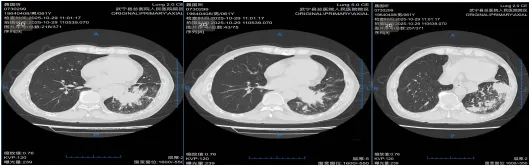

二、胸外科:高难微创,勇克双侧多原发肺癌

胸外科在复杂肺癌手术领域不断突破。一例55岁女性患者,CT发现双肺多发结节,高度怀疑多原发肺癌。面对传统分期手术创伤大、恢复慢的挑战,经多学科(MDT)充分评估、精密协作,胸外科团队勇于创新,成功为患者实施了“单孔胸腔镜下同期双侧肺癌根治术(右肺上叶切除+左肺下叶背段切除+双侧纵隔淋巴结清扫)”。手术一次完成,极大减少了患者痛苦与住院时间。术后病理证实为双侧原发性肺癌,分期分别为IIB期和IA2期。患者术后恢复迅速,第二天即可下床活动,并接受规范的靶向治疗(口服奥希替尼)。至今随访2年,无复发迹象,生活质量高。此案例彰显了我院胸外科在高难度、微创化、个体化肺癌手术治疗方面的卓越实力。

术前右侧胸部肿瘤

术前左侧胸部肿瘤